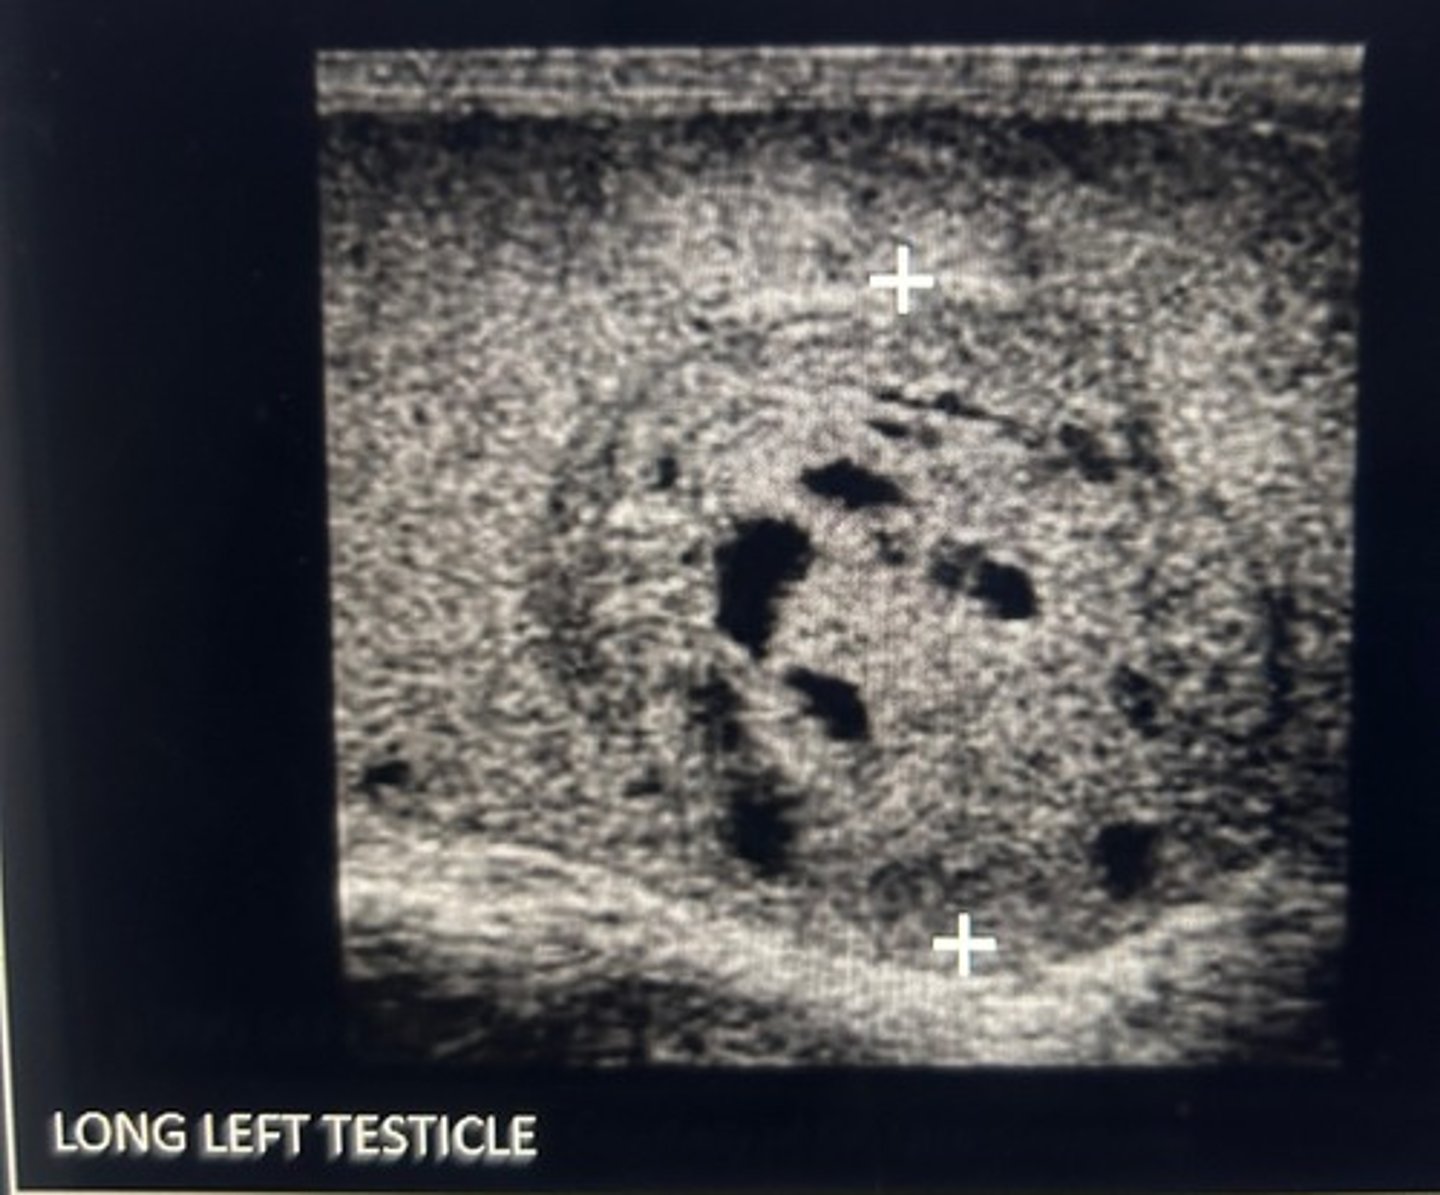

A 3 cm hypoechoic mass is identified in the right testicle. The radiologist request that you perform an abdominal ultrasound. What are you looking for?

Periaortic lymphadenopathy

The first location at a seminoma spreads is to the retroperitoneal lymph nodes. The right gonadal vein connects directly to the IVC so the renal vein would most likely be unaffected by tumor invasion.